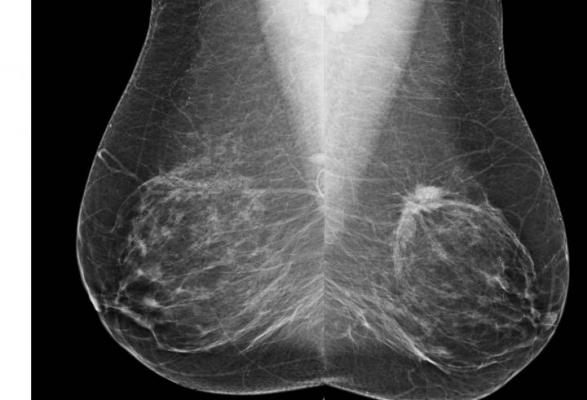

In a study published August 17 in the Journal of Clinical Oncology, researchers updated their current breast cancer risk model, which includes density categories – an important factor in determining the possibility of developing the disease – to one that also includes benign biopsy results.

The researchers, led by Jeffrey Tice, M.D., of UC San Francisco, analyzed data from 1.1 million racially diverse women, aged 35 to 74, undergoing mammography with no history of breast cancer. During follow-up averaging 6.9 years, close to 18,000 women were diagnosed with invasive breast cancer, defined as malignancy that had spread outside the lobules, or milk ducts, and had invaded healthy tissue.